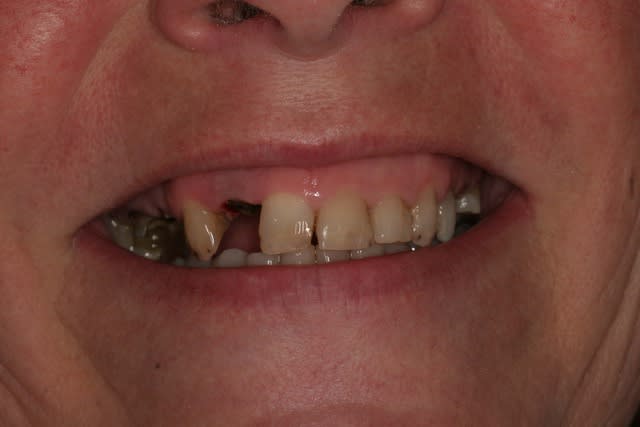

Récemment Céramik râlé, parce qu'il n'y avait pas de nouveau cas (esthétique je crois) à se mettre sous la dent. Je me jettes à l'eau avec ce dernier cas posé ce vendredi (y'a pas plus frais), une larme à l'oeil parce qu'il s'agit aussi du dernier gros cas dans mon cabinet que je quitte cette semaine pour rejoindre ma belle et nos p'tits bouts loin la bas dans le sud.

La patiente a un sourire très médiocre avec migration de plus en plus marqué du bloc incisivocanin sup. Comment l'aidez vous?